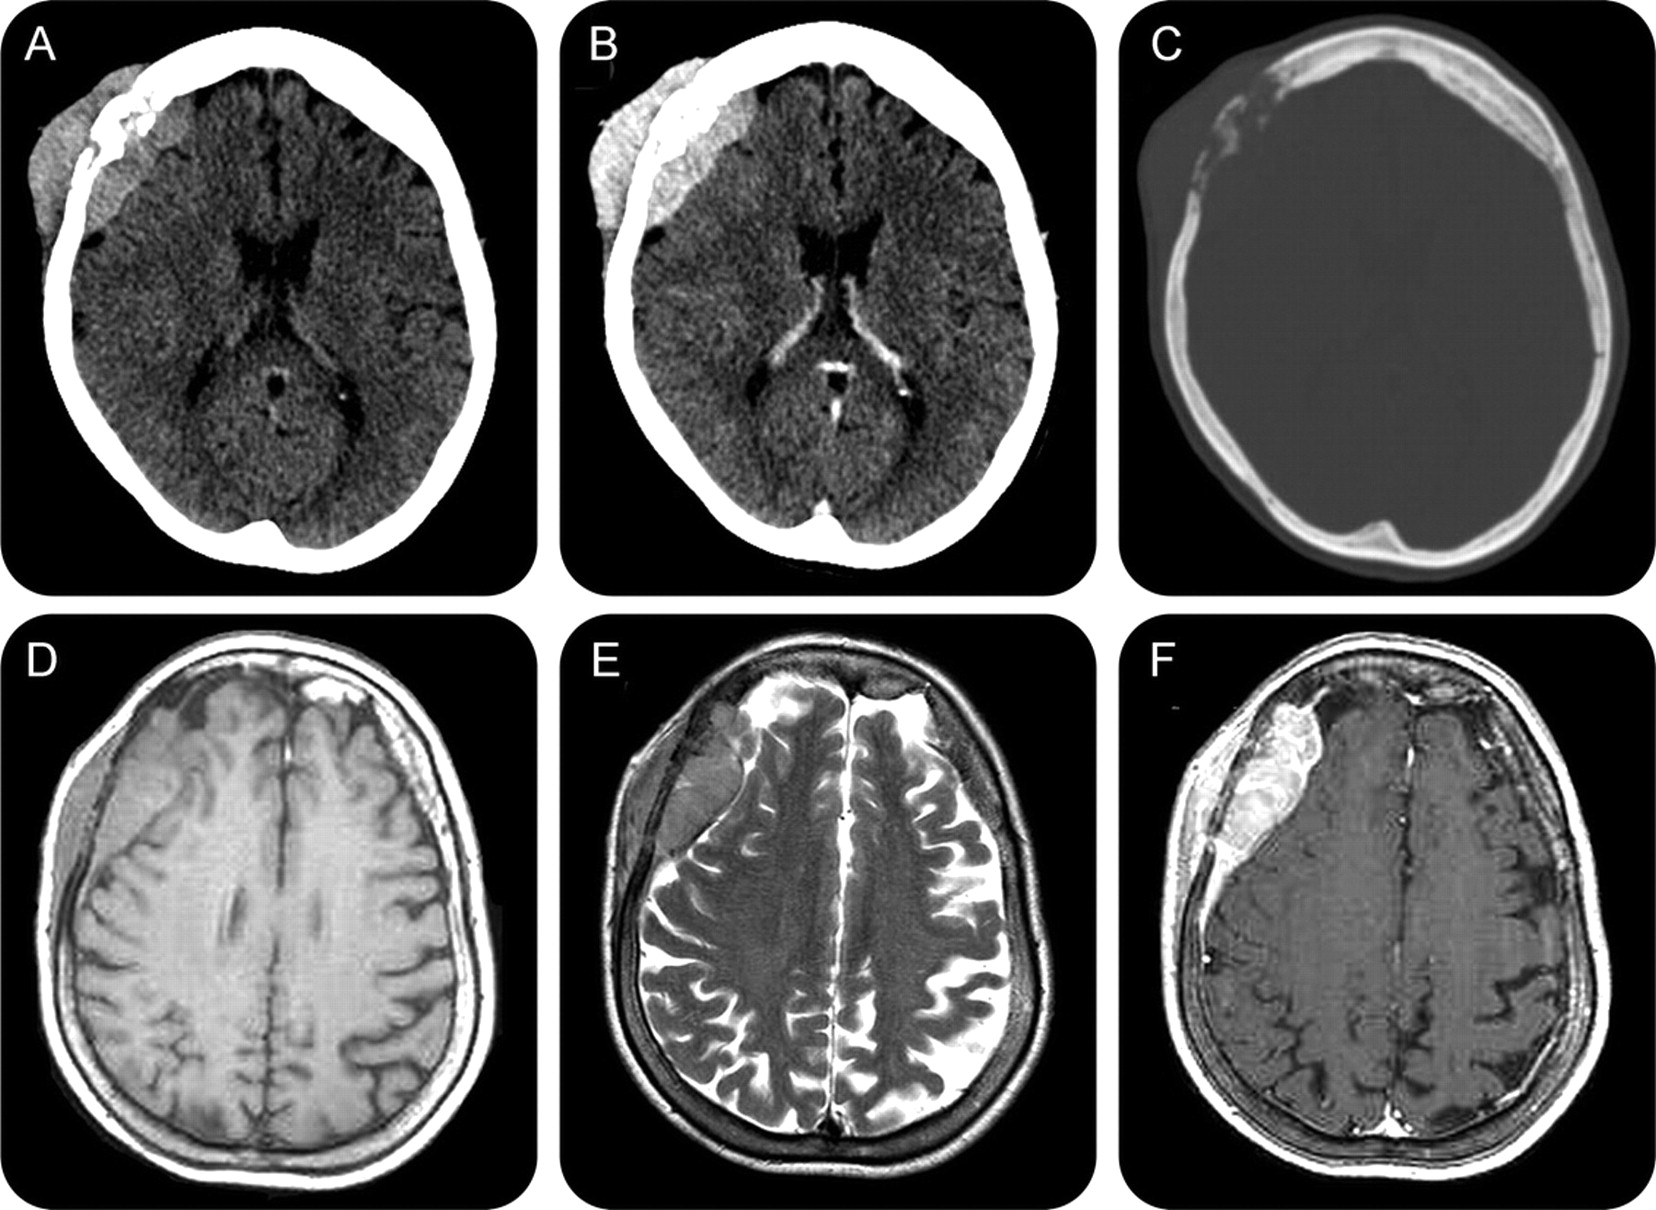

一个67岁的女人面对痛苦的右侧头皮肿胀。大脑成像显示颅内和颅外额质量损伤,骨质破坏当地颅(图)。放射诊断包括恶性脑膜瘤、原发性骨肿瘤和骨转移。胸、腹部、骨盆和轨道CT扫描,骨显像,全身PET,骨髓活检,腰椎穿刺,眼科检查(包括裂隙灯检查)显示没有其他病变。打开病变活检显示弥漫性恶性大b细胞非霍奇金淋巴瘤的硬脑膜、颅骨头。6 R-CHOP周期(利妥昔单抗与环磷酰胺、阿霉素、长春新碱和泼尼松)方案就开始了。主骨(最常非霍奇金淋巴瘤)是罕见的。1、2在我们的例子中,相关的硬脑膜参与(这似乎是次要的)大脑成像和组织学。原发性骨肿瘤通常有一个有利的结果,特别是在治疗疗法相结合。临床阶段是最重要的预后变量在预测总体存活率。